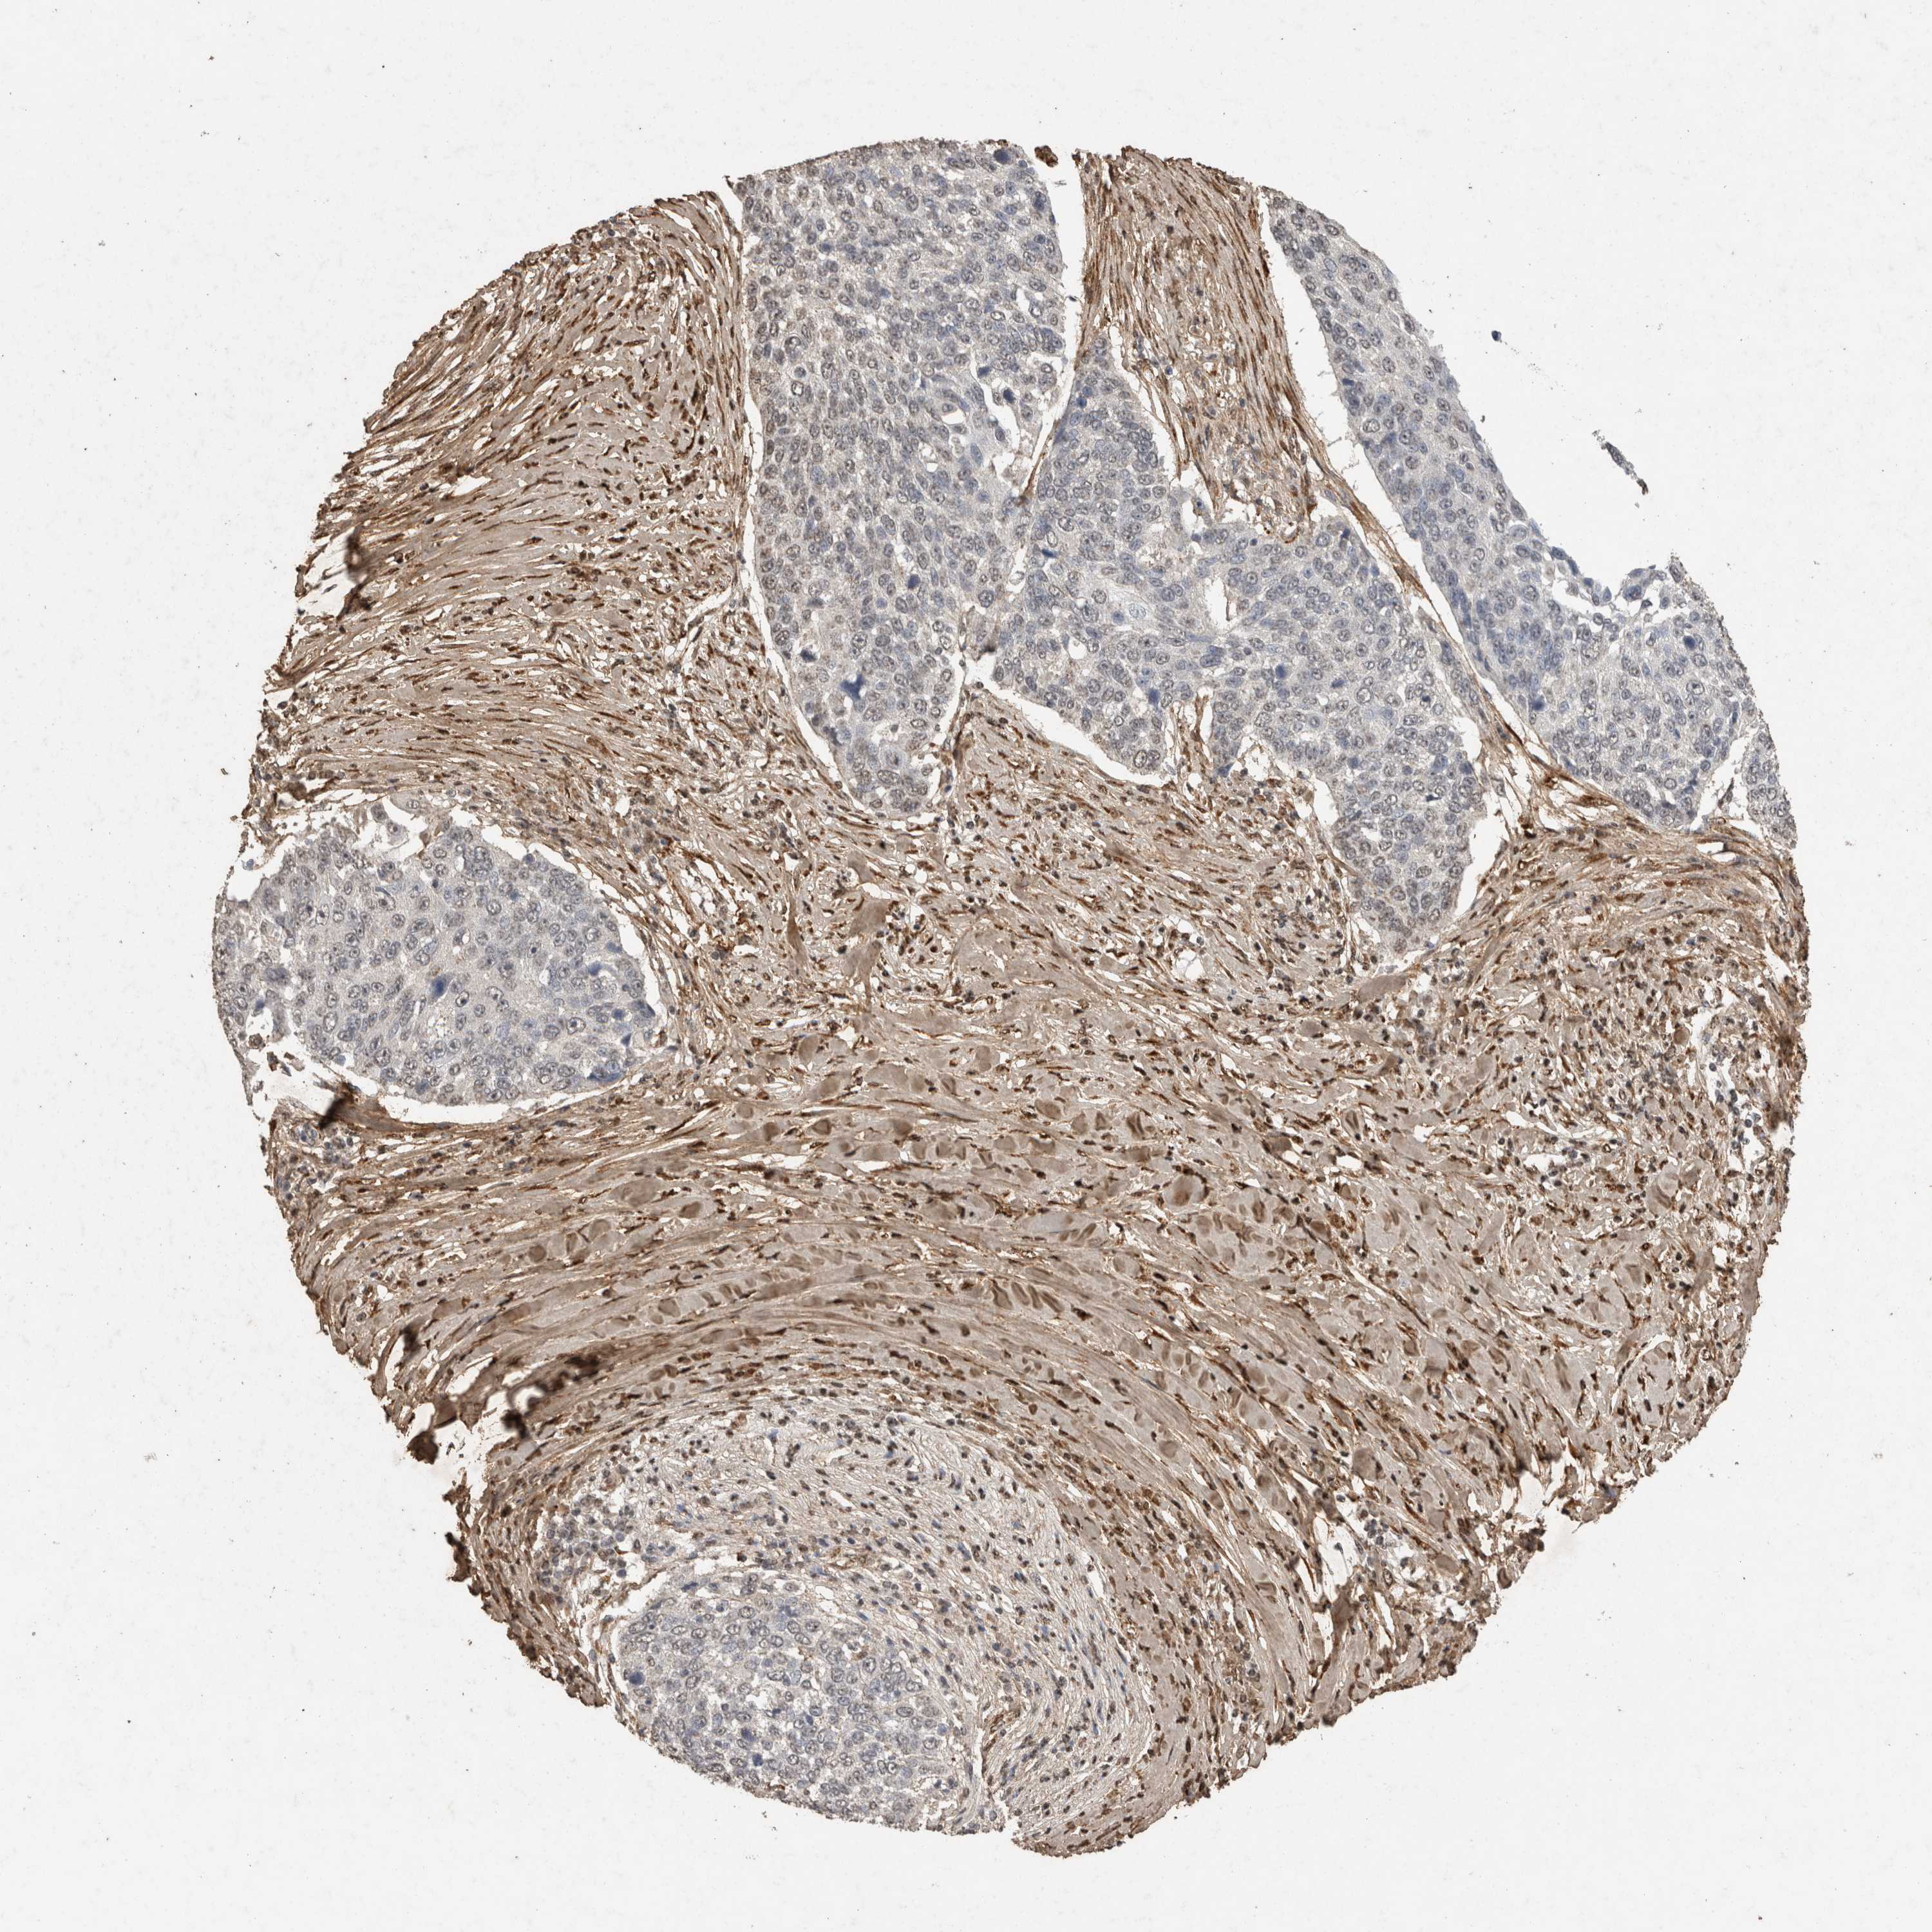

LUNG SQUAMOUS CELL CARCINOMA (TCGA) - Interactive survival scatter ploti

The Survival Scatter plot shows the clinical status (i.e. dead or alive) for all individuals in the patient cohort, based on the same data that underlies the corresponding Kaplan-Meier plots. Patients that are alive at last time for follow-up are shown in blue and patients who have died during the study are shown in red.

The x-axis shows the expression levels (FPKM) of the investigated gene in the tumor tissue at the time of diagnosis. The y-axis shows the follow-up time after diagnosis (years). Both axes are complimented with kernel density curves demonstrating the data density over the axes. The top density plot shows the expression levels (FPKM) distribution among dead (red) and alive patients (blue). The right density plot shows the data density of the survived years of dead patients with high and low expression levels respectively, stratified using the cutoff indicated by the vertical dashed line through the Survival Scatter plot. This cutoff is automatically defined based on the FPKM cutoff that minimizes the p-score. The cutoff can be changed by dragging the vertical line or by entering a cutoff value in the square labeled "Current cut-off".

Under the Survival Scatter plot the p-score landscape (black curve; left axis) is shown together with dead median separation (red curve; right axis). Dead median separation is the difference in median mRNA expression between patients who have died with high and low expression, respectively. It is calculated as follows: median FPKM expression of dead patients with high expression - median FPKM expression of dead patients with low expression. This is intended to aid the user in visually exploring custom cutoffs and the associated p-scores and dead median separation.

Individual patient data is displayed and can be filtered by clicking on one or more of the category buttons on the top of the page. Categories describing expression level and patient information include: high, low, alive, dead, female, male and tumor stages. The scale of the x-axis can be toggled between linear and log-scale by clicking on the "x log" button. Mouse-over function shows TCGA ID, patient information and mRNA expression (FPKM) for each patient.

& Survival analysisi

Kaplan-Meier plots summarize results from analysis of correlation between mRNA expression level and patient survival. Patients were divided based on level of expression into one of the two groups "low" (under cut off) or "high" (over cut off). X-axis shows time for survival (years) and y-axis shows the probability of survival, where 1.0 corresponds to 100 percent.

C1QTNF5 is not prognostic in Lung Squamous Cell Carcinoma (TCGA)

Best expression cut offi

Based on the FPKM value of each gene, patients were classified into two groups and association between prognosis (survival) and gene expression (FPKM) was examined. The best expression cut-off refers the FPKM value that yields maximal difference with regard to survival between the two groups at the lowest log-rank P-value. Best expression cut-off was selected based on survival analysis .

When clicking on this number, the vertical dashed line indicating cut-off, the interactive survival plot, and the Kaplan-Meier curve will be adjusted to show results based on the best expression cut-off.

: 11.67

P scorei

Log-rank P value for Kaplan-Meier plot showing results from analysis of correlation between mRNA expression level and patient survival.

N/A

TCGA RNA samplesi

RNA-seq data is reported as average FPKM (number Fragments Per Kilobase of exon per Million reads), generated by the The Cancer Genome Atlas (TCGA) .

Normal distribution across the dataset is visualized with box plots, shown as median and 25th and 75th percentiles. Points are displayed as outliers if they are above or below 1.5 times the interquartile range. FPKM values of the individual samples are presented next to the box plot.

Average pTPM 18.8

Number of samples 489